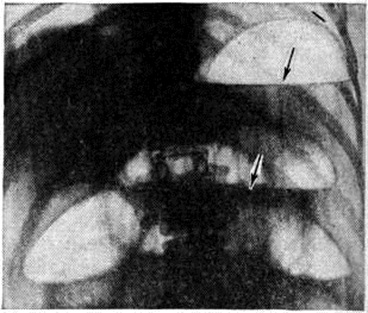

Рентгенологические признаками толстокишечной непроходимости являются значительное расширение просвета толстой кишки и наличие в ней жидкости с горизонтальными уровнями. Толстокишечные чаши отличаются от тонкокишечных характерным расположением — по периферии брюшной полости, в проекции слепой кишки, печёночной и селезёночной кривизны, преобладанием высокого газового пузыря над шириной уровня жидкости и наличием характерных толстокишечных складок.

Информация об Ordo Deus Перейти в оглавление сайта

Рис. 10.

Рентгенограмма брюшной полости при спаечной тонкокишечной непроходимости (положение больного на левом боку): стрелками указаны фиксированные в правой половине живота петли тонкой кишки с газовыми пузырями и уровнями жидкости.